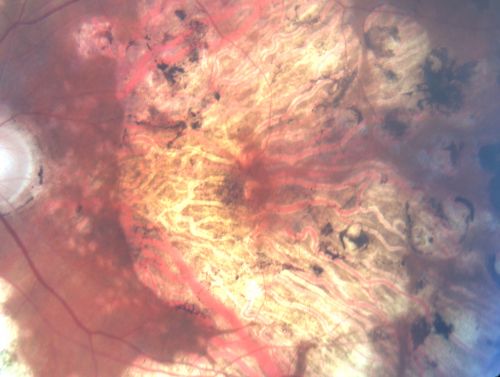

Macular and Peripheral Retinal Scarring from Diabetic Laser Done 25 years previously

72-year-old man had macular and peripheral laser done in the past(1980's)(25 years ago).  His vision, although limited, seems about stable to him.  He is diabetic for 30 years. OD is 20/160, OS  is 20/160.